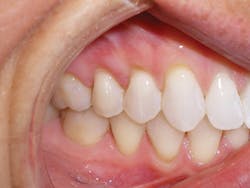

Dr. Miraglia: Fixing Sandra's 'crooked' teeth

Sandra is a common example of a patient having a malocclusion that is the direct cause of her recession, and abfractions. When we first examined Sandra, her chief complaint was her smile (see Figure 3). She was unhappy with her smile and "crooked" teeth and had the desire to fix them.

Sandra expressed to us that she looked into clear aligner therapy but was told she was not a candidate. She was told she would need two years in braces and possibly some teeth extracted. These treatment options were undesirable, so she chose to do nothing. We assured her that she was an excellent candidate for clear aligner therapy, and her treatment time would be 14 months with no extractions.

At the consultation, Sandra's photos were used to teach. The photo of the lower crowding with the lingual plaque and calculus was used to teach Sandra the difference between crowded teeth and aligned teeth. We also informed her that her teeth are not actually "crooked" (her chief complaint). The mandibular occlusal view pointed out her V-shaped arch provided no room for her teeth to fit within the arch.

The remaining photos were used to teach the difference between a good bite and a bad bite. Sandra learned about clefting, recession, abfractions, and the visible areas of enamel wear on multiple teeth. Sandra understood that clear aligner therapy would change her bad bite to a good bite, resulting in a beautiful, healthy smile. My goal went further than that. I knew the benefits of aligned teeth include increased longevity, a healthy periodontium, and proper occlusion for her to enjoy a lifetime of oral health.

Sandra was excited to begin treatment. So her case was submitted, developed, and delivered in short order. Her treatment involved 24 aligners, which took exactly 12 months of treatment time.

Upon completion of treatment, she had a healthy, stable, and functional occlusion. Notice the clefting, recession, and abfraction improvements in the photographs related to her case. This validates my objection to the current standard of care of "waiting and watching" for conditions to worsen. Instead, my hygienists and I educate patients on the long-term solutions of clear aligner therapy so they can make educated choices regarding their oral health.